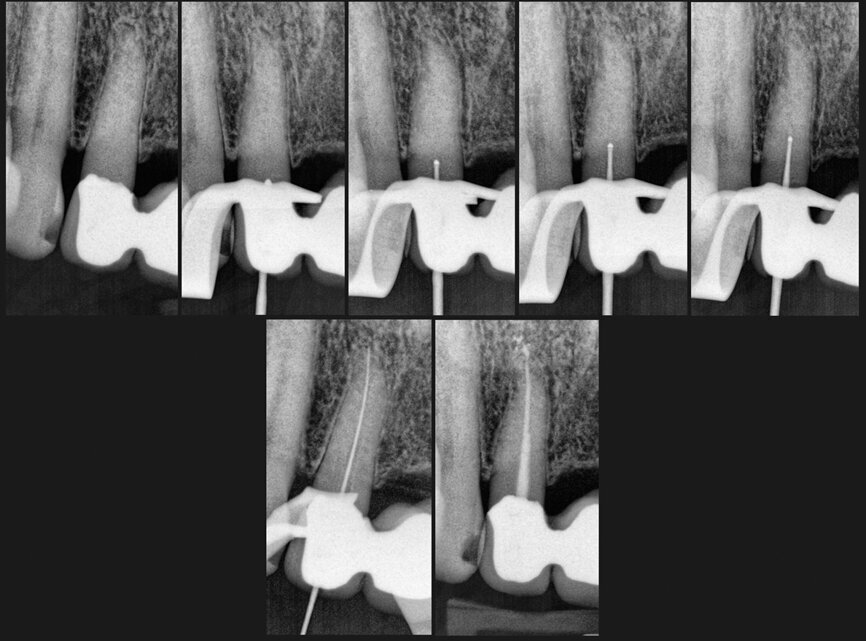

Munce Discovery Burs feature round carbide heads on 31mm (Shallow Trougher) and 34 mm (Deep Trougher) non-flexible shafts that facilitate positive troughing control for locating separated instruments and uncovering hidden canals.

Munce Discovery Burs. (Photo: CJM Engineering)

Along with the newly released diamond-tipped TruGrit Trough Refiner, these longer-than-standard-length burs draw the handpiece head away from tooth structure, creating the favorable geometry that opens a functional view corridor to the deep target area.

In contrast to standard 2.35 mm shaft diameters, the narrow shafts of Munce Discovery Burs — 0.7 mm on the three smallest head sizes and 1 mm on all other head sizes — prevent shaft impingement on deep access cavity walls, significantly reducing ledging and perforation risk while preserving the shaft stiffness required for troughing-type procedures.

In addition, the 0.7 mm shaft diameter on the smallest head sizes allows parallel cement-line dissection around posts and post core-out procedures and offers visibility of the tiny heads in such operations as exploring for calcified canals deep within root structure where visibility would otherwise be blocked by standard-diameter shafts.

Practitioners can uncover hidden canals and expose separated instruments with Munce Discovery Burs 31 mm Shallow Troughers and original 34 mm deep troughers...